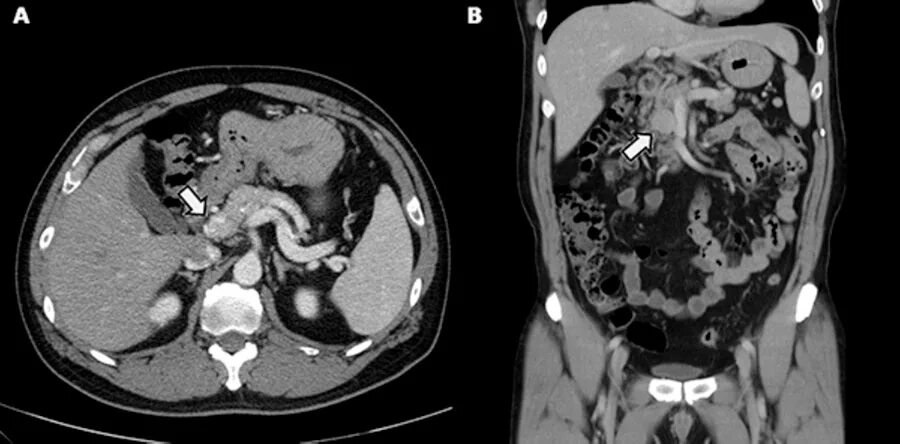

Язва желудка кт